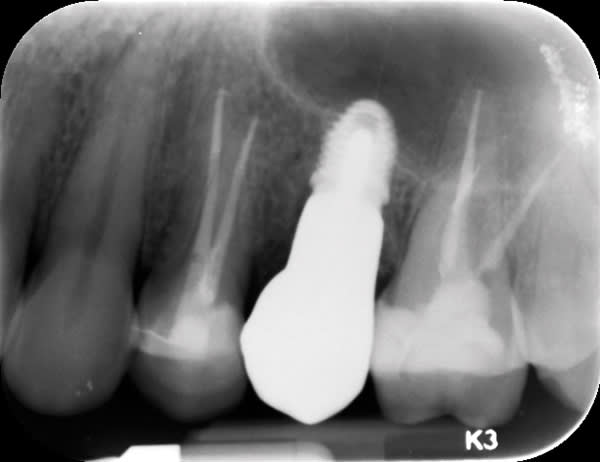

In cases of advanced sinus pneumatization, typically a sinus lift followed by grafting is done to prepare for placement of an implant. This process often requires a longer treatment period and a more invasive procedure than can be achieved with many products and techniques commonly used today. In the case shown (Figure 1 and Figure 2), the patient lacked sufficient bone in the premolar site for placement of an implant of conventional length. By using Southern Implants' Ultra-Short implants, the patient's existing bone could be maximally engaged. Both Ultra-Short implants were 4.5-mm diameter x 4.1-mm long, externally hexed (Figure 3 through Figure 8). Insertion torques of >50 Ncm were achieved.

Ultra-Short implants (≤6 mm) have more than 5 years of follow-up showing a survival rate of 98% in multiple bone classifications, with both immediate and delayed loading in both maxilla and mandible.1